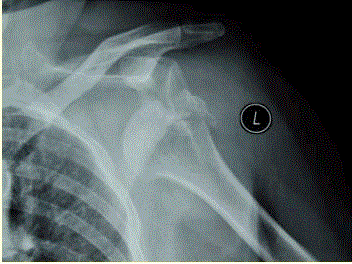

问题 患者女,58岁,左肩关节外伤,医院就诊,行X线检查,如下图。 导致肩关节易脱位的原因包括

选项 A、外伤后盂唇同关节盂分离 B、关节囊前方缺乏韧带和肌肉覆盖 C、肩关节表浅,容易遭受外力打击 D、肩关节活动范围最大 E、关节囊韧带松弛、薄弱 F、肩关节属球窝关节

答案 ABDEF